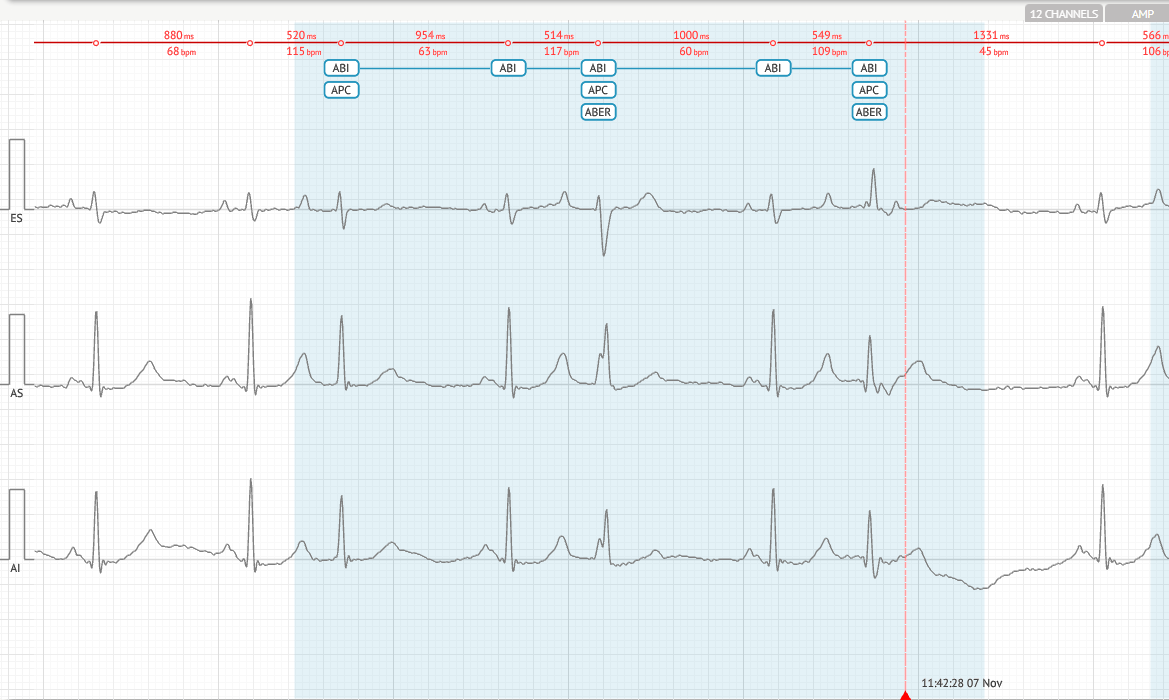

Передсердна Екстрасистолія За Типом Бігемінії - (ПБИ)

Визначення

Кожен нормальний синусовий скорочення супроводжується передсердним екстрасистолієм (ПЕКС).

Критерії

- Після кожного нормального ритму відбувається PAC.